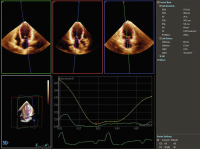

Die standardisierte Echokardiographie: Durchführung, Archivierung und Befunderstellung sowie Evaluierung der systolischen Linksventrikelfunktion // Standardised Echocardiography

Journal für Kardiologie - Austrian Journal of Cardiology 2024; 31 (5-6): 96-103 Volltext (PDF) Summary Abbildungen